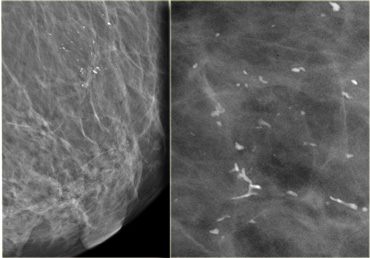

On the left calcifications in a segmental distribution.

Some have a linear distribution and some have a branching morphology.

This is highly suggestive of malignancy (Bi-RADS 4C).

High grade DCIS High grade DCIS

On the left fine linear and branching calcifications in a segmental distribution highly suggestive of malignancy (Bi-RADS 4C).

Extensive high grade DCIS was found at biopsy.